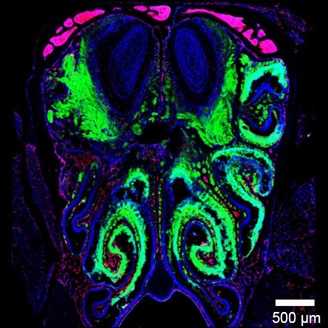

Рисунок 2. Строение обонятельной системы.

(a) — строение обонятельной системы мыши в разрезе. ОЭ — обонятельный эпителий, ОЛ — обонятельная луковица, ЛОТ — латеральный обонятельный тракт.

(б) — cтроение обонятельной луковицы мыши. АК) — аксоны обонятельных рецепторов, ГС — гломерулярный слой, МС — митральный слой, 1 и 2 — внешний и внутренний плексиформные слои обонятельной луковицы.

Тела митральных клеток образуют митральный слой, а аксоны этих клеток формируют латеральный обонятельный тракт. По нему передается информация о запахах в центры головного мозга, которые обрабатывают сигнал. Из-за «доступности» такого способа попадания в мозг, который вдобавок не требует серьезных ограничений по структуре и размерам веществ, данная тема требует более подробного анализа.